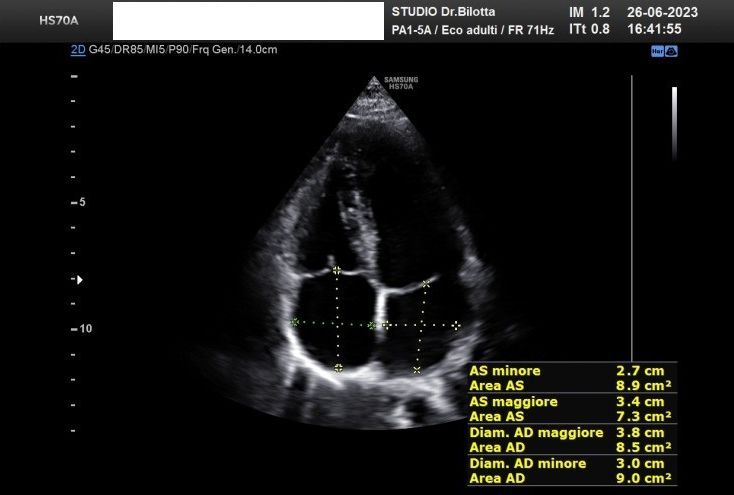

Foto e video